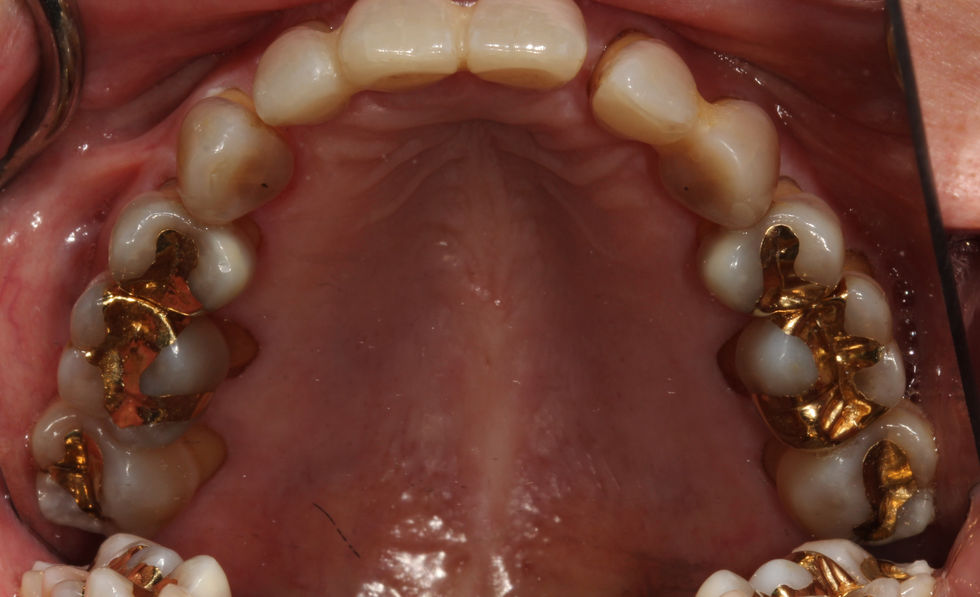

AOX W ceramic implants

AOX case full upper and lower

AOX upper and lower done with full ceramic screw retained implants w Yomi Robot guide.